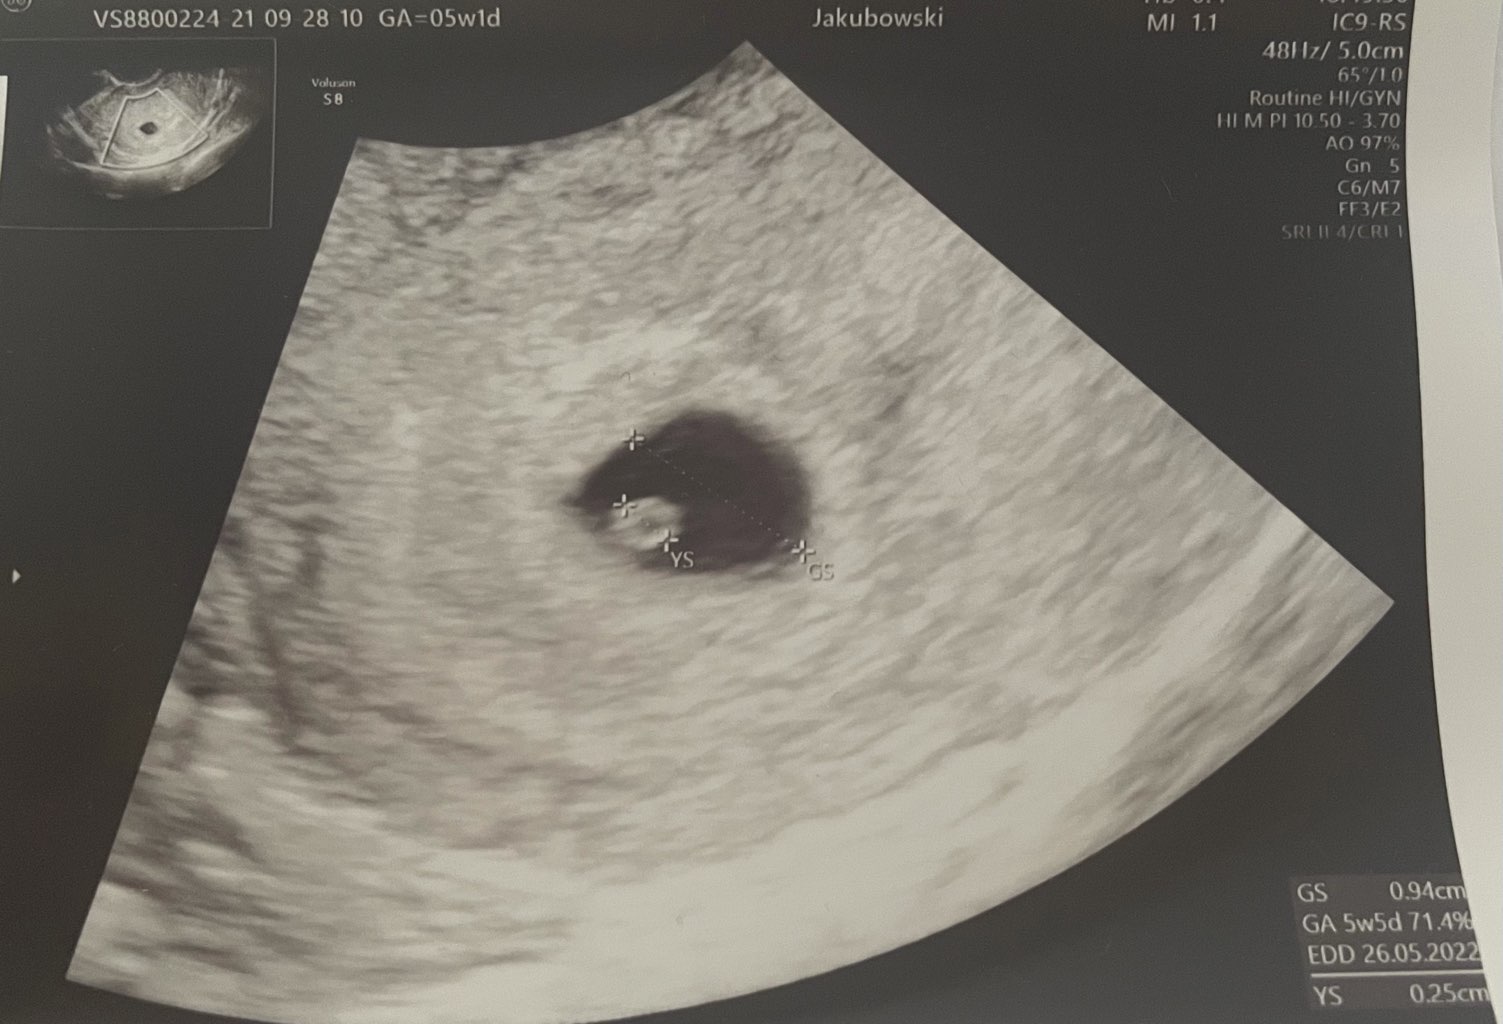

U mnie w 6+0 już ładnie biło serduszko, ale ja mam 26 dniowe cykle i owulacje ok 12 dnia wiec u mnie to szybko sie rozwinęłoJa będę miała wizytę 6+2 i zastanawiam się czy będzie już widoczny zarodekW 5+1 był pęcherzyk i ciałko żółte

U mnie tez ciaza młodsza. Lekarka uspokoiła i powiedziała że często tak się zdarza tymbardziej przy moich dłuższych i trochę nieregularnych cyklach.